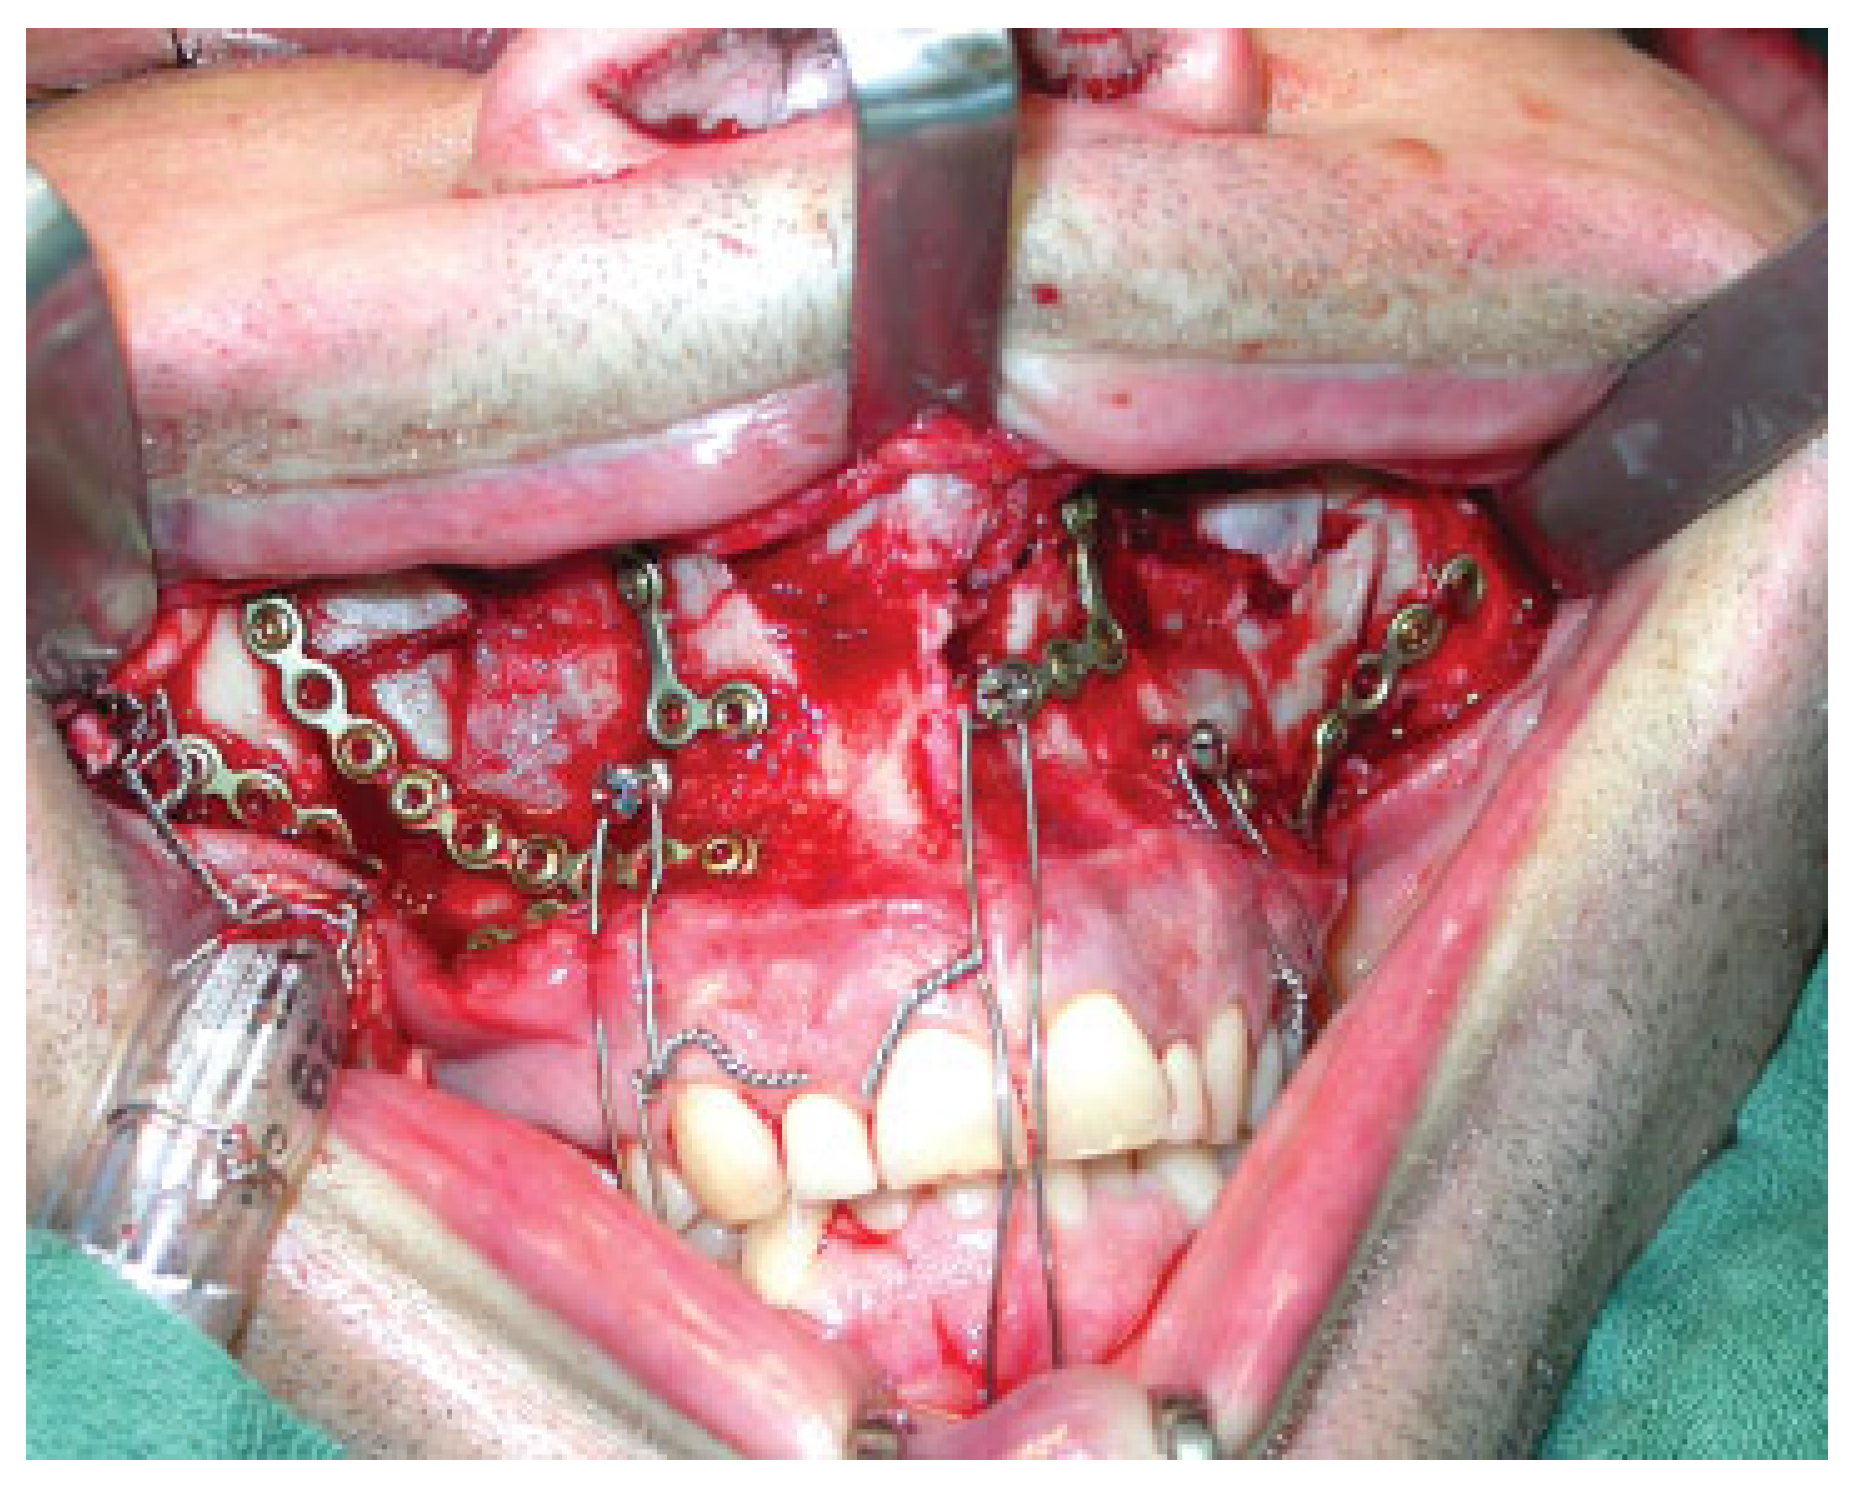

The increasingly popular usage of conventional bone screws with the heads kept at 4 to 5 mm above the mucosa or bone level paved the way for the commercial manufacturing of explicitly designed self-tapping or self-drilling MMF screws during recent years. Among the forerunners of mere single piece MMF screws were screws used in conjunction with stainless steel wire hooks or short, two or three hole, segments of miniplates (“hanger plates”). The coupled hooks or the empty plate holes served as anchors for MMF ligatures (Figure 1). An example still of interest is the spino-mental fixation, where two screws fitted with hooks are positioned below the anterior nasal spine and shortly above the mental protuberance to establish MMF in a very simple manner [8,9].

Figure 1. “Hanger plates” for mandibulo-maxillary fixation (MMF). Short plate segments fixed transmucously with cortical bone screws are used as fasteners for the intermaxillary wire ligatures. “Hanger plates” were among the forerunners of specialized MMF screws.